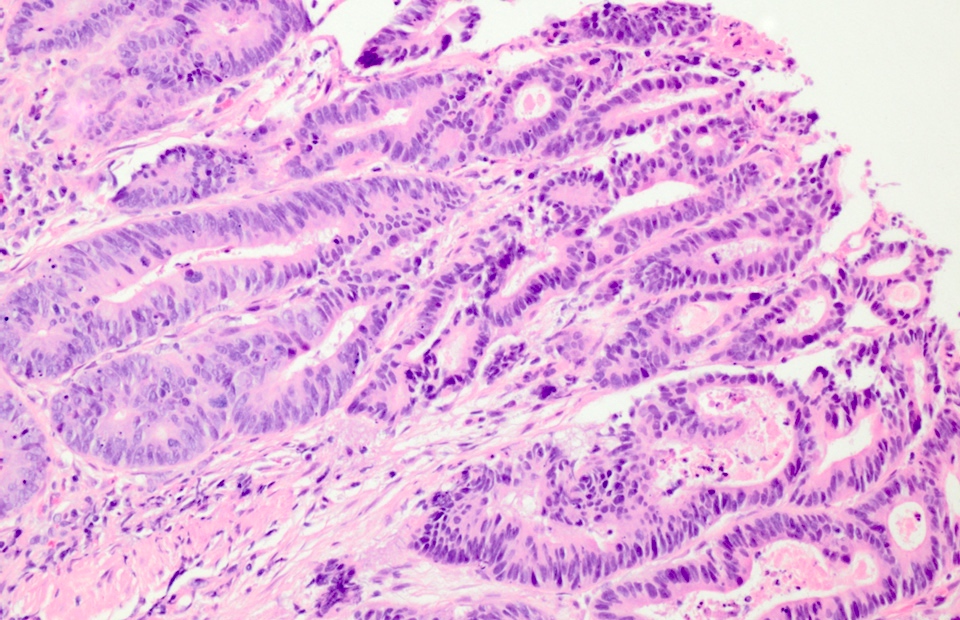

Microscopic (histologic) description

- High grade dysplasia:

- May show complex architecture, such as cribriform glands

- Loss of nuclear polarity

- Nuclear pleomorphism, vesicular nuclei and prominent nucleoli

Microscopic (histologic) images